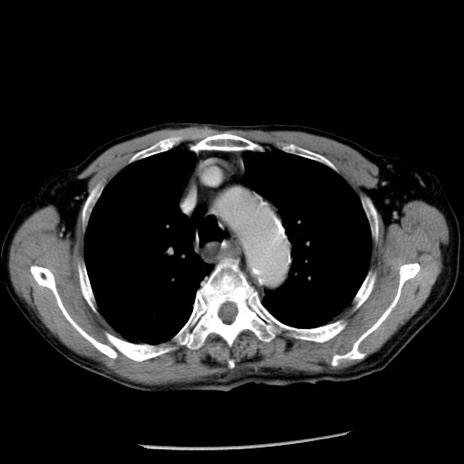

症例26(横断像)

【症例】80歳代男性

【主訴】嘔吐

【現病歴】昨晩2回嘔吐あり、今朝になっても嘔吐あり。来院。

【既往歴】胃潰瘍

【身体所見】意識清明、BT 37.6℃、BP 166/95mmHg、HR 100bpm、SpO2 97%、腹部:平坦・軟、腸蠕動音聴取良好、圧痛なし。

【データ】WBC 21900、CRP 1.46